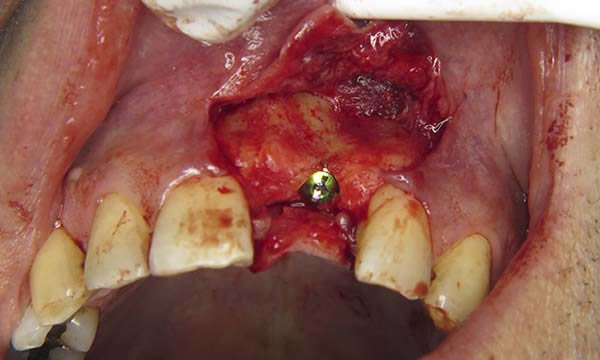

A case of a patient who was a long term resin retained bridge wearer. The resin retained bridge was placed after the patient lost his UL1 many years ago. There was a history of the resin retained bridge lute failing, and due to the loss of the UL1 there was a labio - palatal bone deficit.

A clear acrylic position guide was used to guide implant placement within the aesthetic envelope and guided bone regeneration was used labially to elevate the long standing concavity. A Bonded crown was used to restore the implant and at the 12 month follow up, the bone level around the implant remains unchanged and the patient is confidently smiling.

Case C

During Treatment